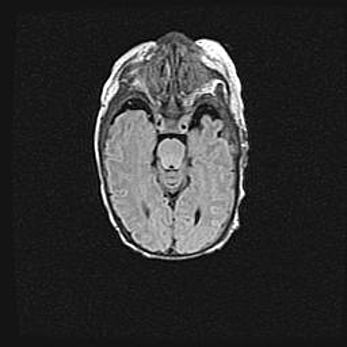

Подострая гематома правой гемисферы мозжечка.

Наружная гидроцефалия.

Возраст: 15 дней

Вес: 3100 г

Пол: женский

Окружность головы: 37 см

Срок гестации: 35-36 недель

При открытой наружной форме гидроцефалии у новорожденных расширяются и переполняются субарахноидные пространства.

Кровоизлияния в мозжечок имеют две клинико-анатомические формы: полушарные гематомы и кровоизлияния в червь.

К появлению этой патологии может привести: повреждения головного мозга, возникающие в результате асфиксии и гипоксии плода при беременности, или травмы во время родов. Редко гематома мозжечка может быть результатом первичной коагулопатии и сосудистой мальформации, диссеминированном внутрисосудистом свертывании, изоиммунной тромбоцитопении.